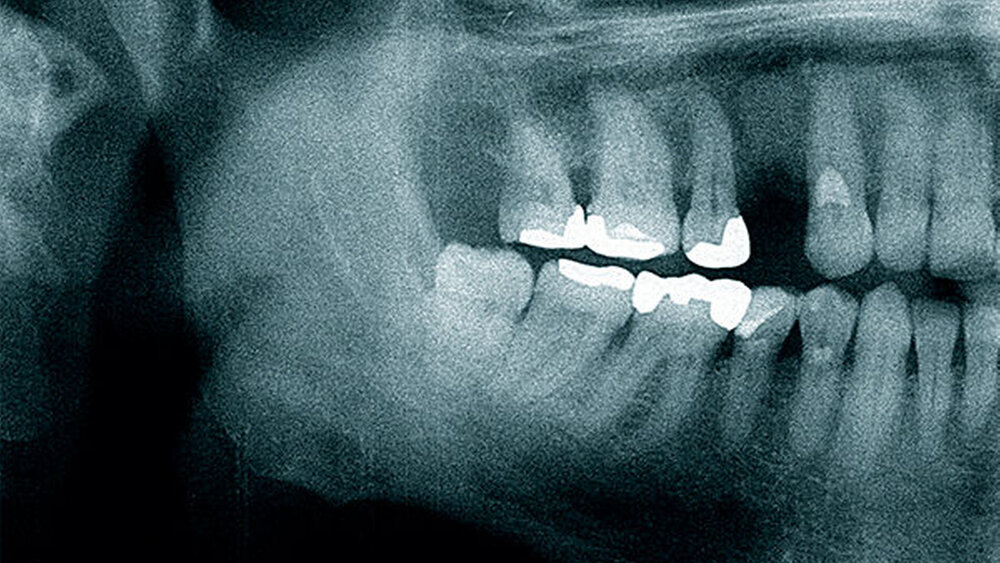

Der folgende klinische Fall dokumentiert die Behandlung eines 61 Jahre alten Patienten, der sich initial mit erheblichen Beschwerden an Zahn 14 vorgestellt hatte. Die radiologische Untersuchung (Abb. 1) ergab eine periapikale Aufhellung sowie eine insuffiziente Wurzelkanalbehandlung. Im Folgenden wurde die Krone entfernt und eine Revision der Wurzelkanalbehandlung durchgeführt. Im Rahmen der Revisionsbehandlung stellte sich eine Längsfraktur im Bereich der vestibulären Wurzel dar. Aufgrund der daraus resultierenden schlechten Prognose einer weitführenden konservierenden Therapie wurde der Zahn atraumatisch entfernt und die Alveole sorgfältig von Granula‧tionsgewebe und einem sich apikal befindenden Zystenbalg befreit (Abb. 2). Das gewonnene Gewebe wurde der histopathologischen Untersuchung zugeführt; dabei ergab sich das Bild einer radikulären Zyste. Aufgrund der latent vorhandenen Inflammation im Bereich der Alveole wurde auf eine sofortige Augmentation mit Knochenersatzmaterial im Sinne einer Ridge Preservation verzichtet. Die Alveole wurde konventionell mit einem Kollagenkegel und einer adaptierenden Naht versorgt. Nach Besprechung mit dem Patienten wurde eine implantatprothetische Versorgung geplant. In der ersten chirurgischen Phase (sechs Wochen nach der Extraktion) erfolgte ein horizontaler Alveolarkammaufbau mittels GBR-Technik unter Lokalanästhesie, um das abgebaute Knochengewebe wiederherzustellen und damit ein entsprechendes Implantatbett zu gestalten. Präoperativ zeigten sich vestibulär in regio 14 sowohl der Knochen als auch das Weichgewebe defizitär (Abb. 3). Im Rahmen der geplanten Augmentation erfolgte die Bildung eines lokalen Mukoperiostlappens in regio 14. Aufgrund der aus den vorhergegangenen operativen Eingriffen resultierenden Narbenzüge im OP-Gebiet wurde auf eine gängige Lappenextension über das Augmentationsgebiet hinaus verzichtet. Nach Lappenbildung konnte der wandige Defekt exploriert und intensiv mit physiologischer Kochsalzlösung gespült werden (Abb. 4). Im Anschluss erfolgten die Vorlage einer neuen nicht resorbierbaren Membran (permamem, botiss biomaterials, Zossen, Deutschland) sowie der Zuschnitt der Membran entsprechend der Größe des abzudeckenden Defekts (Abb. 5). Es folgte die Augmentation des wandigen Knochendefekts mit allogenem Knochenersatzmate‧rial (maxgraft spongiöse Granula, botiss biomaterials), das zuvor mit venösem Eigenblut des Patienten durchmischt worden war (Abb. 6 und 7). Danach wurde das Augmentat mit der vorgelegten nicht resorbierbaren Membran abgedeckt (Abb. 8). Der Wundverschluss erfolgte mittels horizontaler Matratzennaht und Einzelknopfnähten (Resolon 4.0/5.0, Resorba, Nürnberg, Deutschland) (Abb. 9). Die postoperativ angefertigte Halbseiten-Panoramaschichtaufnahme zeigte eine vollständige Augmentation der Defektregion (Abb. 10).

Die klinische und radiologische Verlaufskontrolle sechs Monate nach der GBR zeigte eine suffiziente Weichgewebssituation sowie ein solides knöchernes Implan‧tatlager in regio 14 bei mehr als 8 mm periimplantär fixierter Gingiva (Abb. 12 und 13). Für die eigentliche Implantation wurde ein Mukoperiostlappen geringer Ausdehnung gebildet und der augmentierte Bereich anteilig wiedereröffnet. Eine gute knöcherne Regeneration der ehemaligen Zahnalveole wurde dabei sichtbar (Abb. 14). Die allogenen Knochenpartikel waren fest in das neugebildete Knochengewebe integriert, Anzeichen von Bindegewebseinkapselung waren nicht sichtbar. Ein Titanimplantat (Straumann Bone Level Tapered, Institute Straumann AG, Basel, Schweiz) wurde mittels Bohrschablone gemäß der 3D-Planung an Position 14 – 2 mm subkrestal – inseriert und einer geschlossenen Einheilung überlassen (Wundverschluss Resolon 6.0, Resorba, Nürnberg, Deutschland). Die Implantatposition wurde postoperativ mittels Panoramaschichtaufnahme überprüft (Abb. 15). Vier Monate nach der Insertion wurde das Implantat freigelegt und ein individualisierter PEEK-Gingivaformer eingesetzt (Abb. 16). Bereits drei Wochen später folgte die prothetische Versorgung mithilfe einer verschraubten Metallkeramikeinzelkrone auf einem Titanimplantataufbau (Abb. 17 und 18). Eine Individualisierung der Farbgebung im Bereich des Kronenhalses wurde seitens des Patienten bei der Anprobe abgelehnt. Die Position der Krone wurde radiologisch dokumentiert und dient, zusammen mit den entsprechenden Sondierungstiefen, zur Verlaufskontrolle der Umbauvorgänge im Bereich des periimplantären Gewebes (Abb. 19).